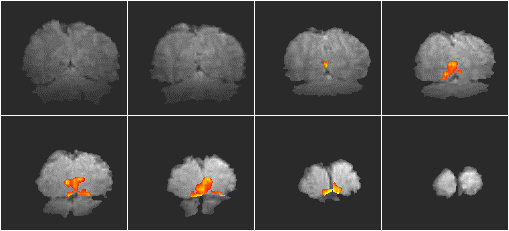

The resulting activation map is shown in Figure 5.13. The coloured regions represent the regions that correlate well to the stimulus (p>0.05). The background images are the average of the actual fMRI data set, so that the resolution seen in these images is the same as that of the activation maps. Regions of activation can be seen in the primary visual cortex and visual association areas. The change in the primary visual cortex upon activation was approximately 20%.

Figure 5.13 High resolution two shot interleaved EPI functional images for a visual stimulus in the right visual field. Activation (p>0.005) is overlaid on the average of the images used for the fMRI analysis.